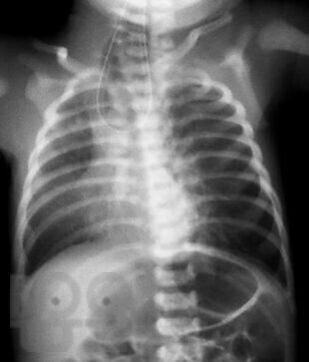

В пособии рассматриваются современные принципы диагностики и лечения хирургических заболеваний новорождённых и детей первого года жизни, возможных осложнений и исходов. Акцентируем внимание студентов на эмбриогенез, этиологию и патогенез, классификацию, клинические проявления и выбор методов лечения. Пособие содержит вопросы для самоконтроля и список литературы для дополнительного изучения.

Пособие подготовлено по дисциплине «Детские хирургические болезни» в соответствии с Федеральным государственным образовательным стандартом высшего профессионального образования для студентов V, VI курсов, обучающихся по основным образовательным программам - программам специалитета по специальности «Педиатрия» и для студентов, обучающихся по основным образовательным программам - программам специалитета по специальности «Лечебное дело».